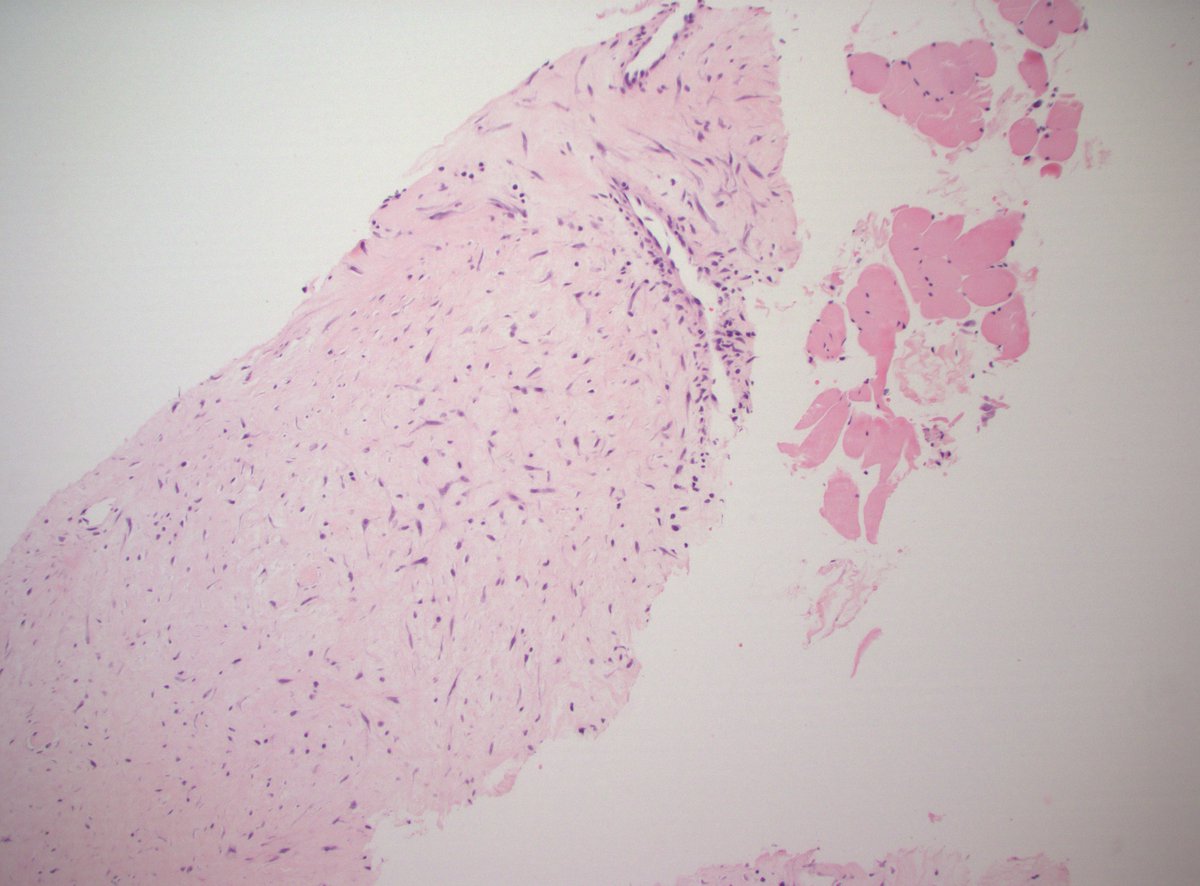

This was a curbside consult from #dermpath. Patient has a history of mastectomy for breast cancer and is now presenting with a chest wall skin nodule. What is your diagnosis? - IHC: p63 @wusm_pathology WashU Medicine Pathology & Immunology Education #breastpath #PathTwitter #PathX